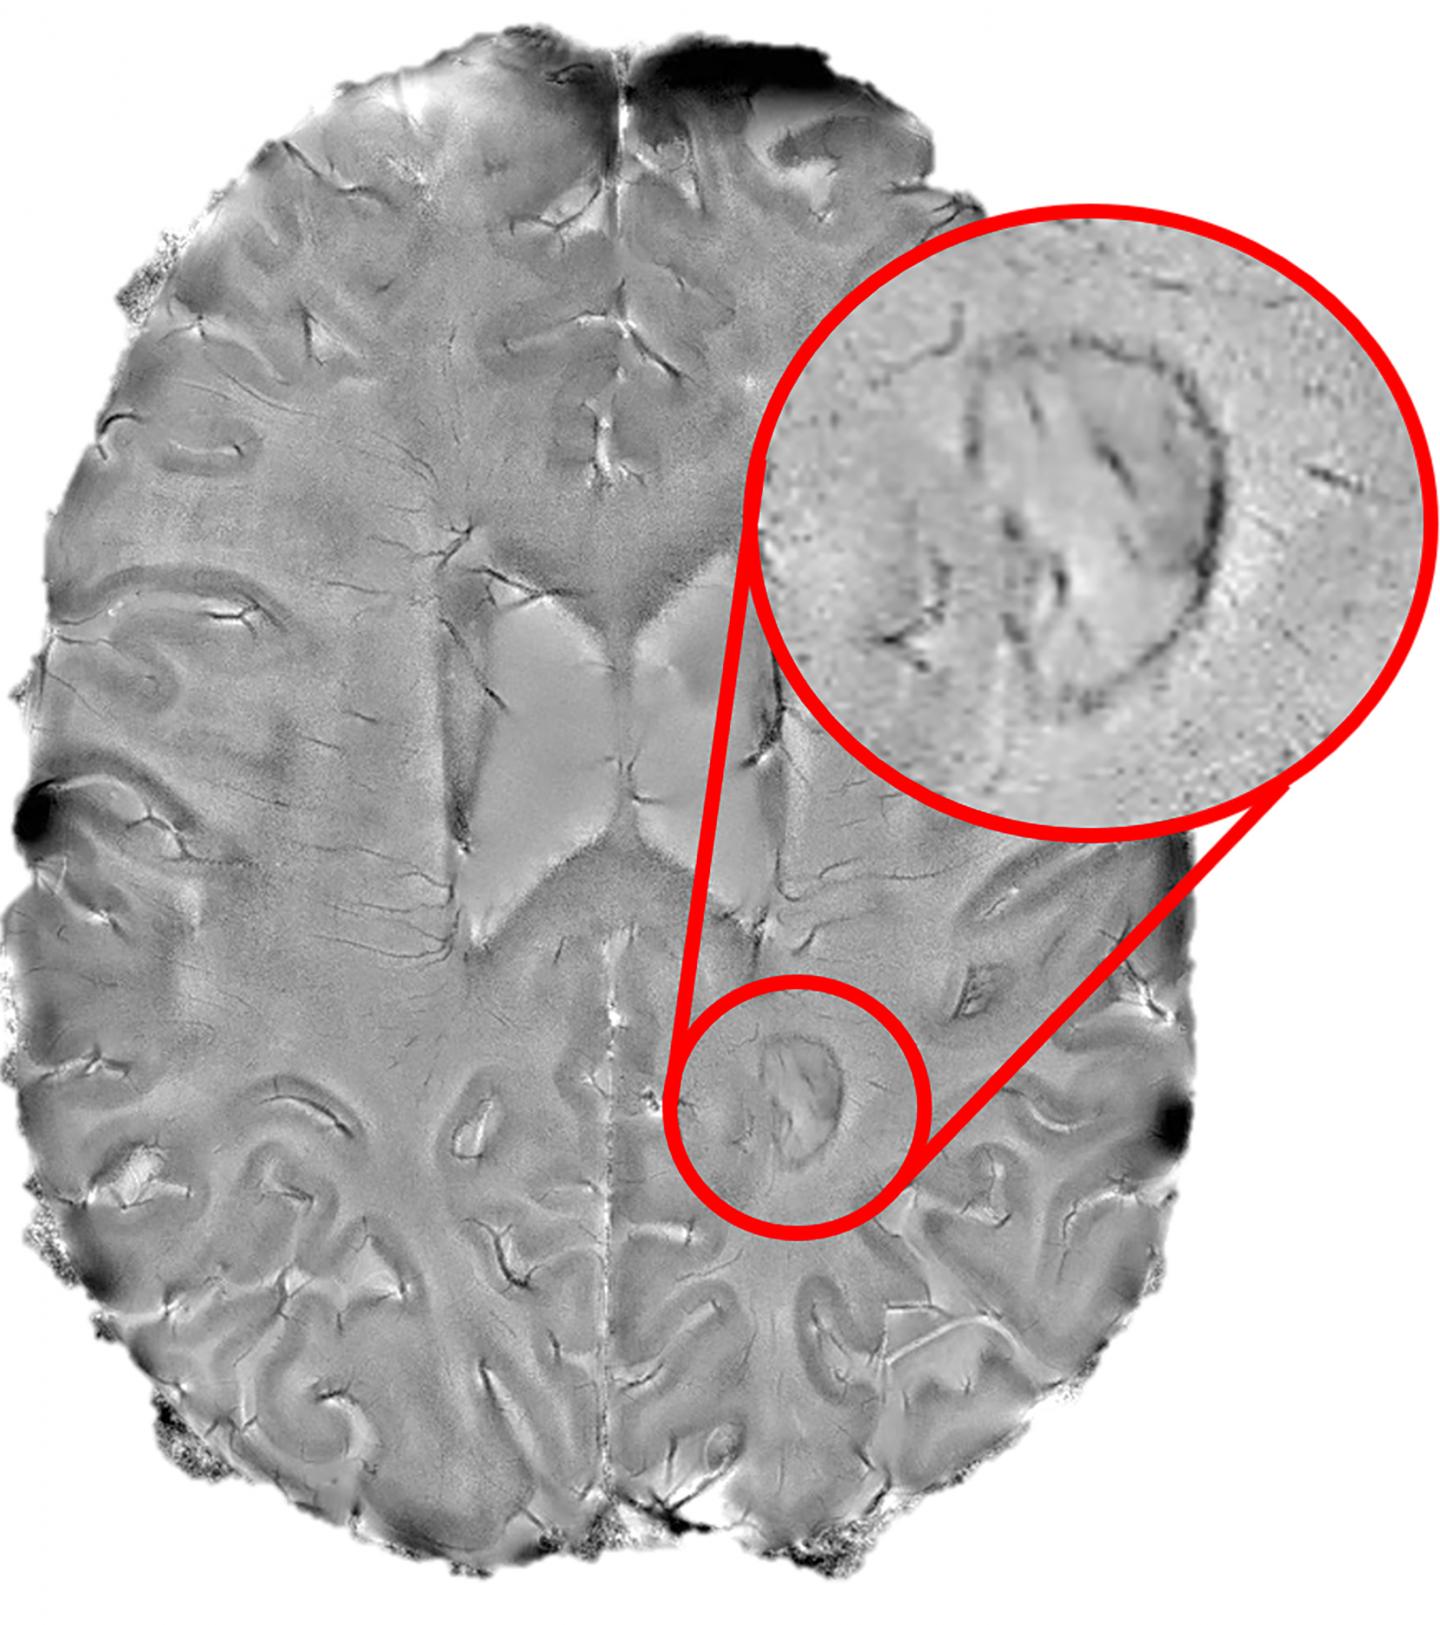

image: NIH researchers found that dark rimmed spots representing ongoing, "smoldering" inflammation, may be a hallmark of more disabling forms of multiple sclerosis.

Aided by a high-powered brain scanner and a 3D printer, NIH researchers peered inside the brains of hundreds of multiple sclerosis patients and found that dark rimmed spots representing ongoing, "smoldering" inflammation, called chronic active lesions, may be a hallmark of more aggressive and disabling forms of the disease.

Doctors often use magnetic resonance imaging (MRI) to diagnose patients as the immune system's attack produces lesions that appear as spots on scans of patients' brains. While some of the lesions heal, completely or partially, other lesions remain and rimmed ones appear to actively expand, or "smolder", for many years. Nevertheless, until recently, researchers did not fully understand the role chronic active lesions play in the disease, in part, because it was difficult to find the ones that remain chronically inflamed.

Starting in 2013, Dr. Reich's team showed that by using a high-powered, 7-tesla MRI scanner, they could accurately identify damaging, chronic active lesions by their darkened outer rims, in agreement with previous studies.

Finally, the team used a 3D printer to compare the spots they had seen on scans to the lesions they observed in brain tissue samples autopsied from a patient who had passed away during the trial. They found that all expanding rimmed spots seen on the scans had the telltale features of chronic active lesions when examined under a microscope.